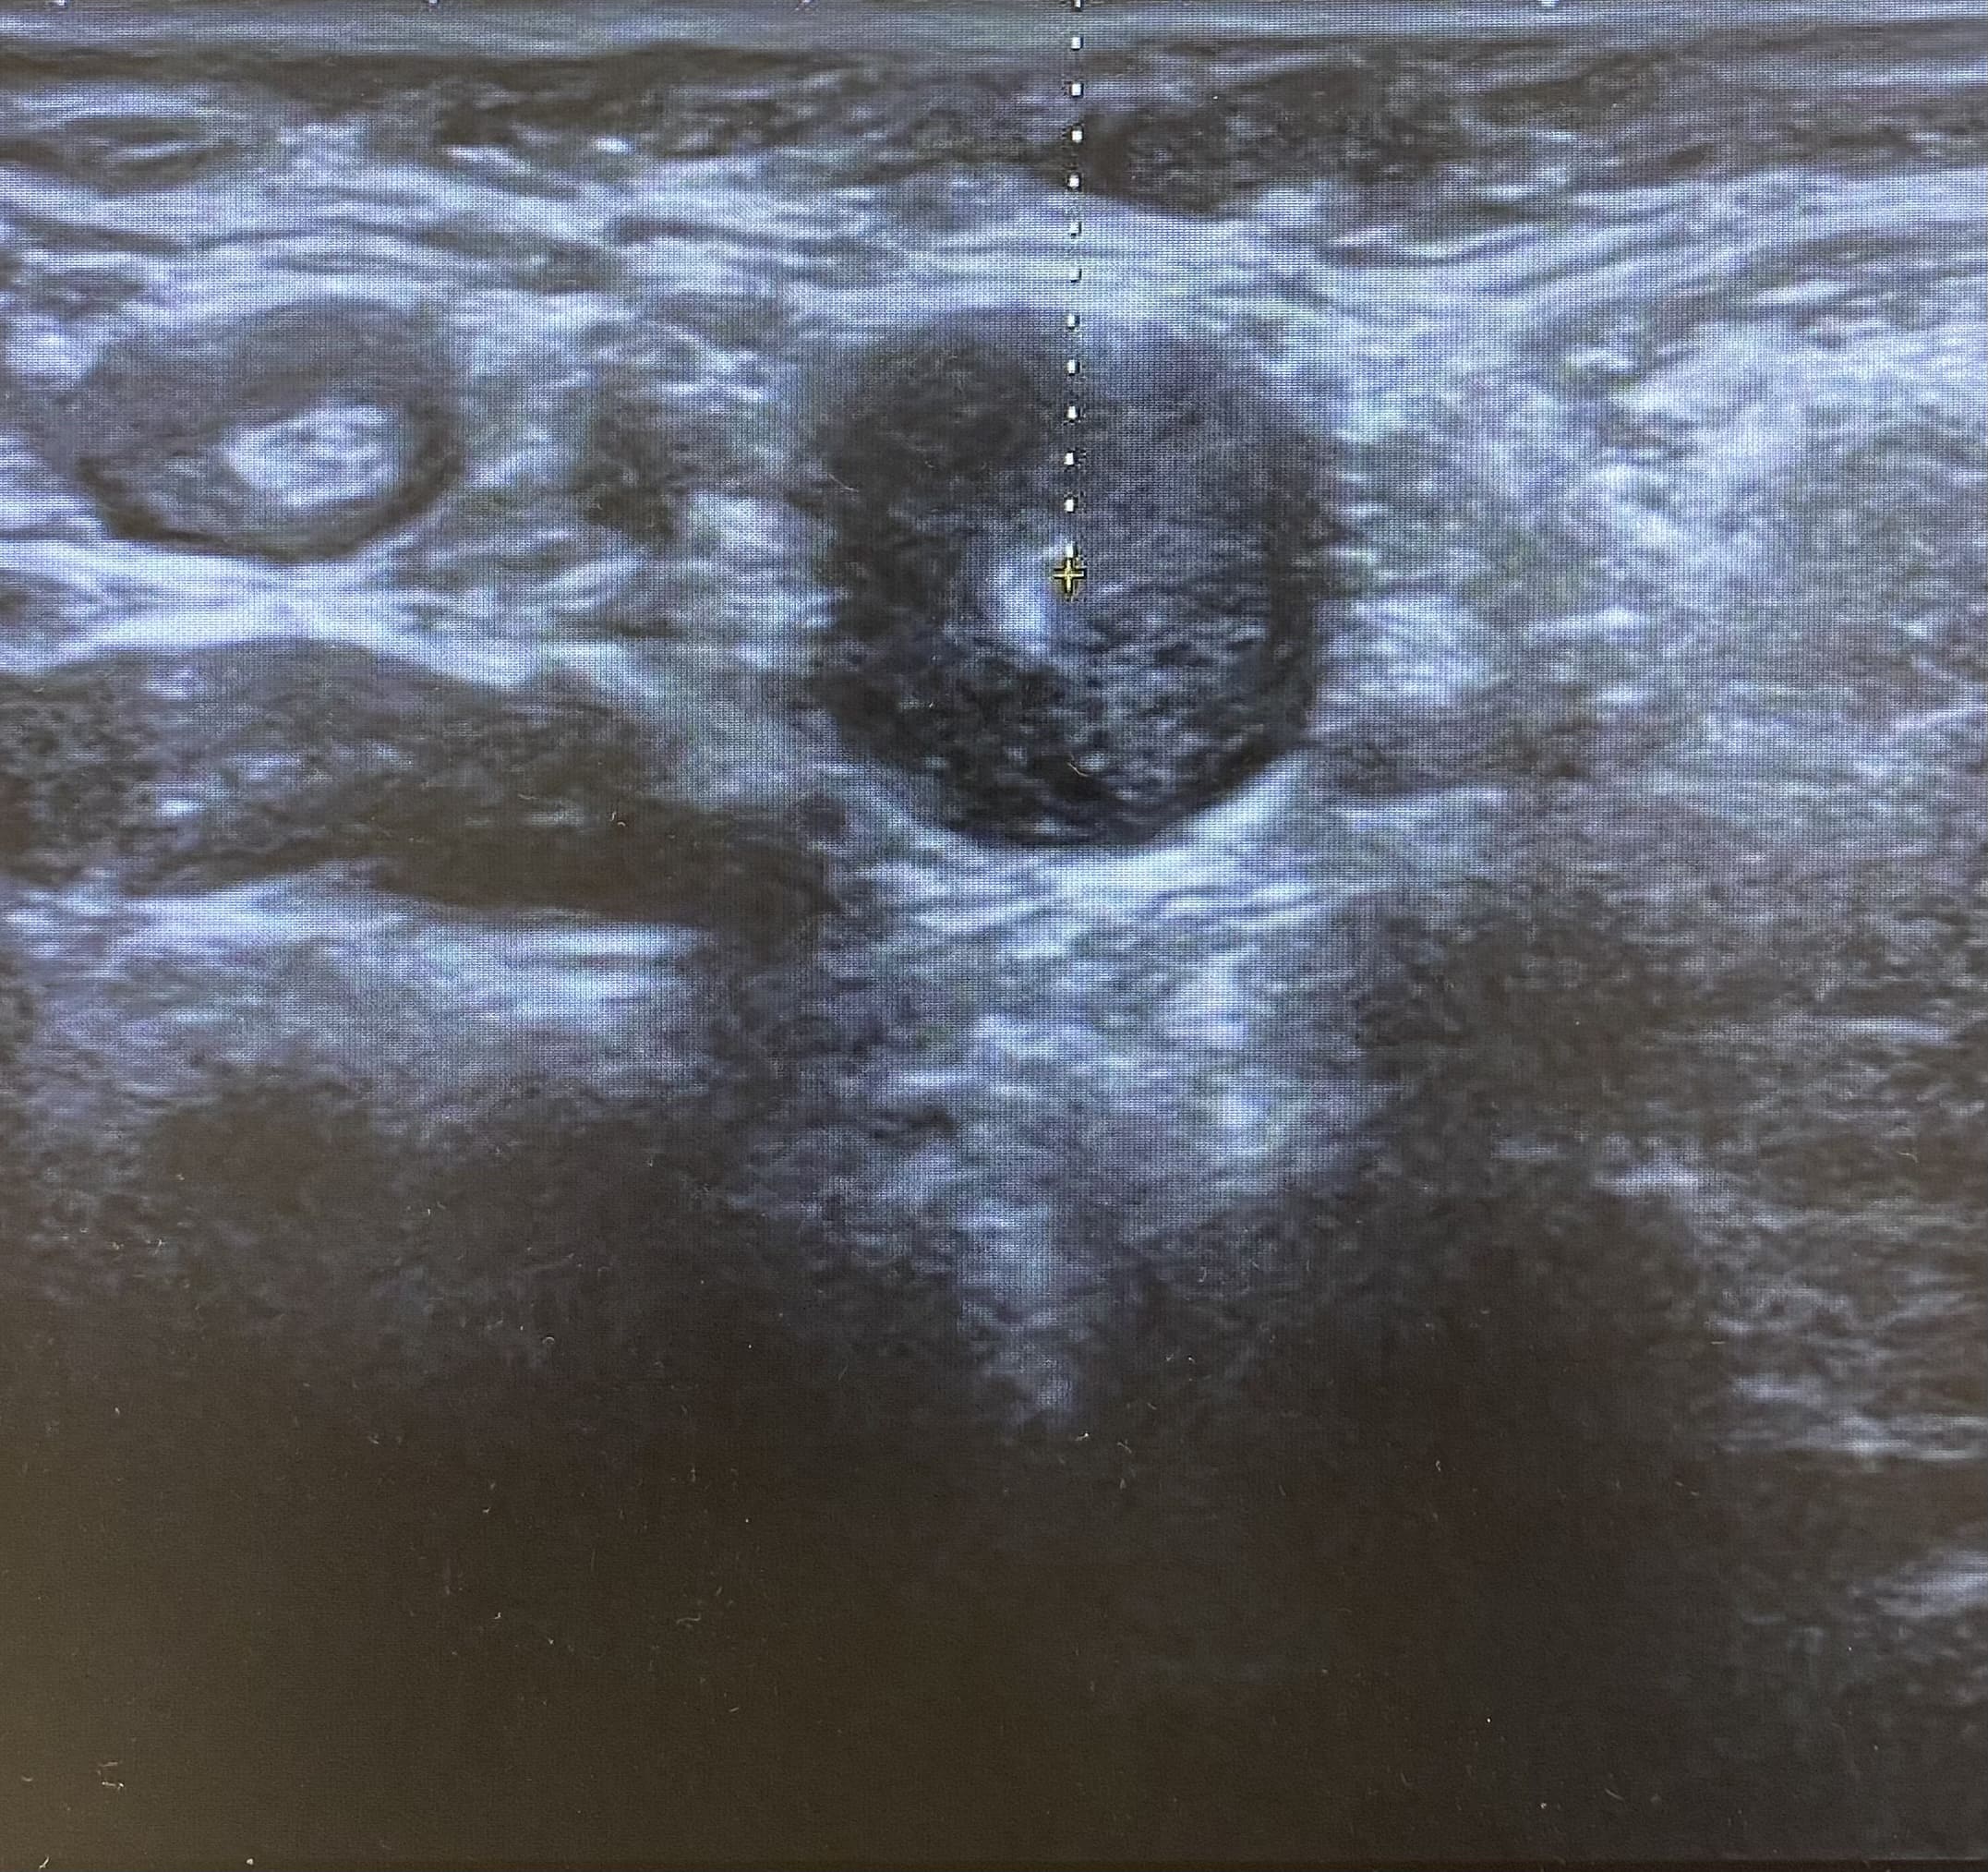

Ecografía: Valoración de adenopatías para acercamiento diagnóstico (típicas/atípicas).

Adenopatías patológicas, algunas redondeadas, con eje anteroposterior > 1 cm, parénquima homogéneo, cortical engrosada aunque con hilio respetado.

Ecografía axilar: múltiples adenopatías con eje corto > 2 cm y cortical engrosada.